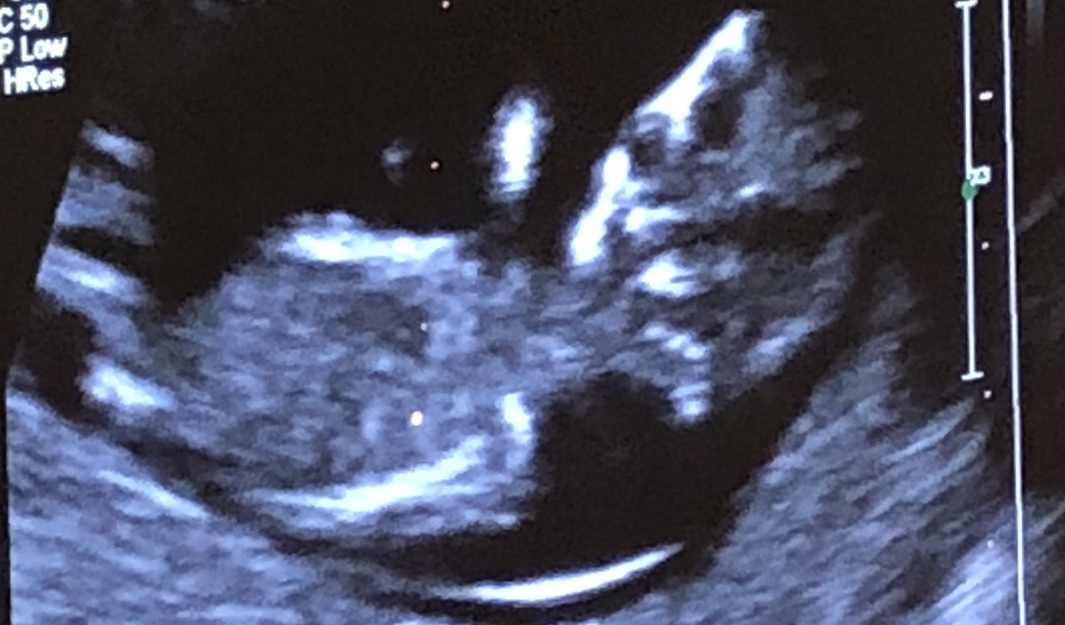

i’m putting up 12 weeks scan image!! gynea wasn’t able to determine baby’s gender yet. would grealt appreciate any opinions!! thanks heaps!! :)

Think baby is turned to face you 😂 can't see nub